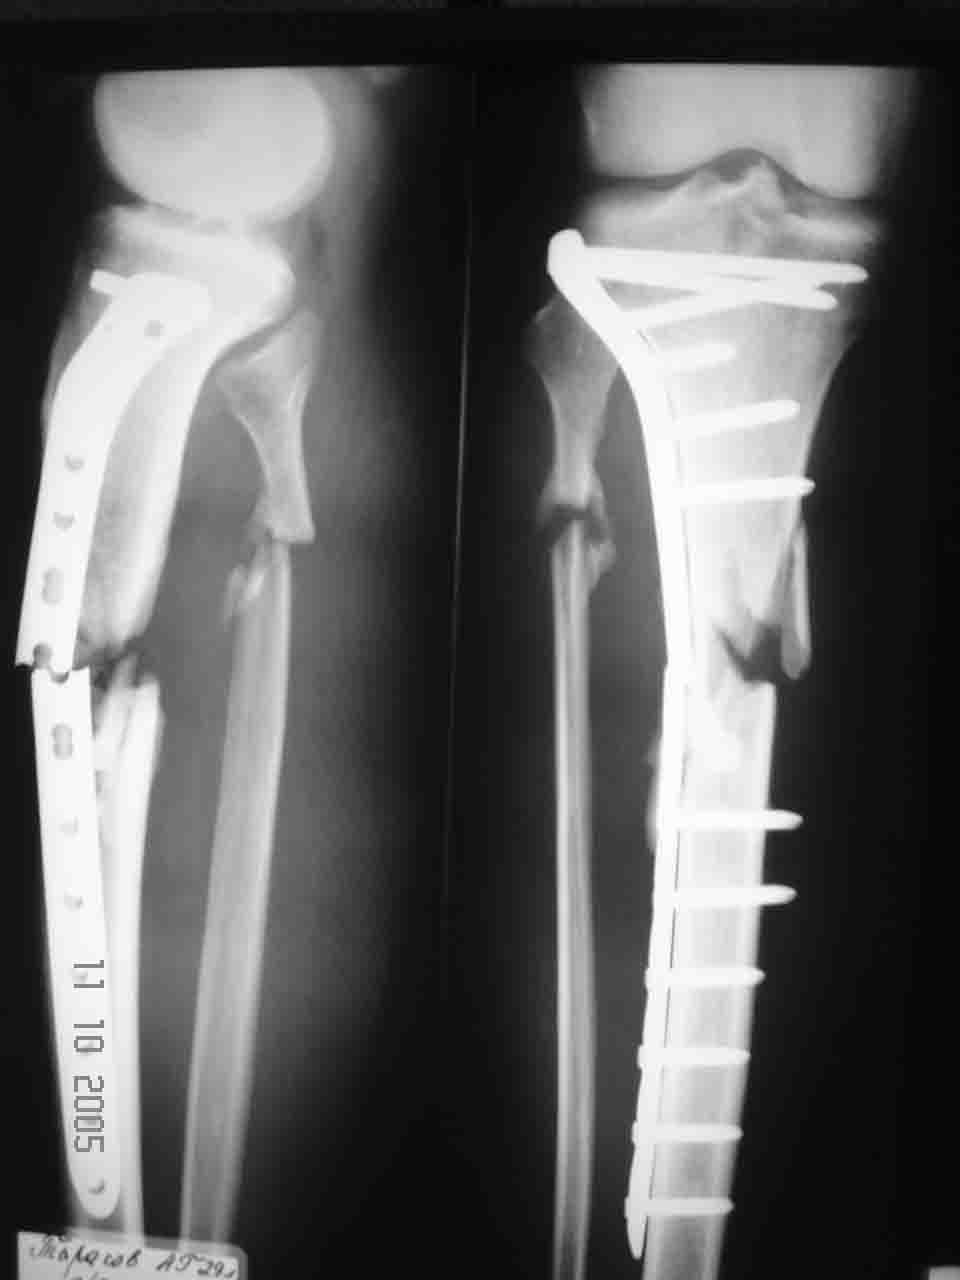

Уважаемый Алексей, глядя на Р-граммы левой голени фиксированной пластиной создается впечатление, что имеется дефект б/берцовой кости. Учитывая это при ЧКО необходимо выполнить костную пластику дефекта. В противном случае кость даже после консолидиции останется слабой, что приведет к повторному перелому. Мне кажется, что в данном случае предпочтителен ЗИО б\берцовой кости с рассверливанием костномозгового канала и блокированием, т.к. при ЗИО активизируются процессы регенерации за счет гематомы в области перелома, что приводит к образованию параоссальной костной мозоли. Плюс к этому в кости будет находится прочный фиксатор, который очень редко ломается и не беспокоит пациента.

Да не так уж он короток, ~8-9 см. Все отверстия любого гвоздя будут выше зоны несращения. Конечно, винтов в центральный отломок лучше ввести побольше.

Причина перелома - на мой взгляд - неадекватная репозиция. Сегмент удлинен, об этом говорит диастаз между отломками малоберцовой кости. Отсюда и впечатление "дефекта". Он есть, но вторичен.

Что делать сейчас? Наш опыт показывает, что в таких случаях между отломками находится плотный соединительнотканный рубец, надежды на перестройку которого в костную ткань минимальны. Поэтому - открытая репозиция и спонггшиозная аутопластика.

Фиксация - на ваш вкус. Показаний к ВКДО тут пожалуй никаких, а вот пластина или гвоздь - это уж как вам нравится.